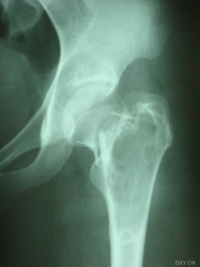

常发生于5到15岁的儿童,男性发病多于女性,比率约为2:1。病变部位多在长骨的干骺端。最常见部位为肱骨近端,其次为股骨近端。活动性(active相对具有侵袭性的)骨囊肿靠近骨骺区,随着儿童年龄增大,病灶会逐渐远离骨骺,成为非活动性(inactive)。在年龄超过17岁的患者,病变会在非长管骨发生,如跟骨、骨盆等。

有经验的骨肿瘤医生仅凭X线平片就可以作出骨囊肿的临床诊断。病变灶为边界清晰的液性低密度灶,四壁为薄层的硬化灶壳。病变灶略向近骨骺的干骺部位扩大。病灶非偏心性,也不破坏骨外壳,更不会突破骨质形成骨膜外反应骨,除非是在病理骨折后的愈合期。有时脱落的骨皮质成份落入囊腔中,X片显示被称为“落叶征”(FallenleaforFallenfragment)。当病灶发生在骨盆,CT扫描对病灶部位及囊肿形态的判断有价值。MRI可以明确囊内富含的液性成分。骨ECT扫描表现为外周薄的浓集而中央病灶冷区。

1.好发于4-20岁,多见于5-15岁儿童,少见于成人。好发于股骨颈、股骨上端和肱骨上端。随着年龄增长,囊肿逐渐向骨干方向移动。

3.X线摄片显示长骨干腄端或骨干部位有椭圆形溶骨破坏,边界清楚,其周围可见薄层硬化带,骨皮质可有轻度膨胀变薄。

3.X线摄片显示长骨干骺端有椭圆形密度均匀的透明阴影,病变局限,与

正常骨质间有明显界线,骨皮质膨胀变薄。

X线表现病损为界限清楚的射线透亮区,外有一薄层骨硬化边缘,由于囊肿膨胀性生长,造成骨皮质不规则变薄,X线片常呈假分叶状表现,尤多做囊肿在肱骨或股骨的干骺端向下扩展至骨干,向上扩展虽接近骨骺,但后者可被累及,病理性骨折很常见,囊肿可有骨嵴假象,病理检查见病损为单房的囊腔,其中充满清液,囊内衬以薄层纤维组织,骨折后腔内含血性液体并出现骨痂。

X线平片位于长骨干骺端,呈圆形、卵圆形或柱形,沿长骨纵轴发展,表现为轻度膨胀性生长,局部骨皮质变薄,边缘光整,无骨膜增生。合并病理骨折时,骨碎片向囊内移位,称“碎片陷落征”,有助于鉴别。

主要通过X线片及病理来诊断。X线片示,多发生于长管状骨的干骺端,髓腔中心呈圆形或卵圆形的透光区,边缘清晰而硬化,长轴与骨的长轴一致,多呈中心性生长,无骨膜反应,可见一锐利透光线横过骨病损区。病理:囊内可有少量黄色或血性稀薄液体,囊肿壁内衬一薄层纤维组织,囊内可有骨嵴分隔。镜下见囊壁由成纤维细胞、多核细胞和胶原纤维构成。